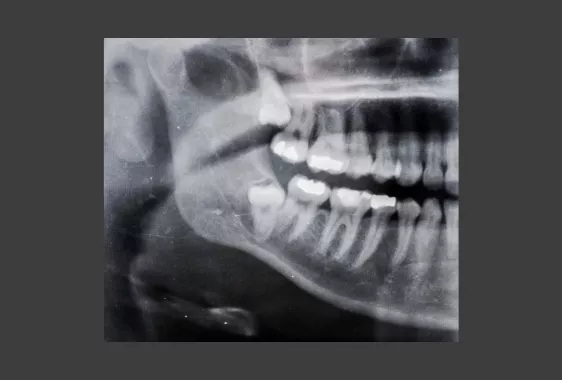

Простой информативный метод определения положения восьмерок – панорамный снимок челюсти. Когда встает вопрос о наличии воспаления, кисты, новообразования, специфического строения корней, назначается дентальная компьютерная томография. Теоретическая информация представлена для ознакомления. Окончательно узнать можно только на консультации в стоматологии. Придя в «Реферта» на осмотр, вы сразу сможете пройти обследования на месте, получить подтверждение и рекомендации по зубам мудрости.